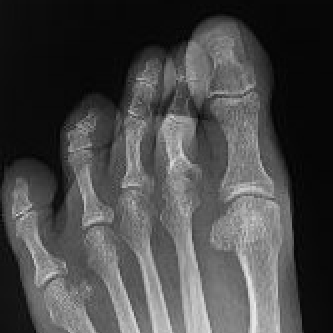

Hammer toe

Definition

Plantar flexion deformity PIPJ with dorsiflexion of the MTPJ

Associated with Hallux valgus

Hammer toe associated with severe hallux valgus